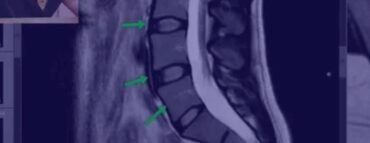

План видеоурока

- Что оценивать на МРТ

- Как выглядит идеальный позвоночник

- Как выглядит плохой позвоночник

- Как выглядит позвоночник спортсмена

- Надрыв кольца на МРТ, поясничный прострел

- Протрузия на МРТ

- Грыжа осложненная стенозом канала

- Секвестрированная грыжа

- Артроз на МРТ

- Позвоночник пациента, занимающегося тяжелым физическим трудом

- Остеопороз, перелом позвонка

- Кисты на суставах

- Гипертрофия фасетки

- Листезы

- Гемангиомы

- Гипертрофия желтой связки

- Грыжа Шморля